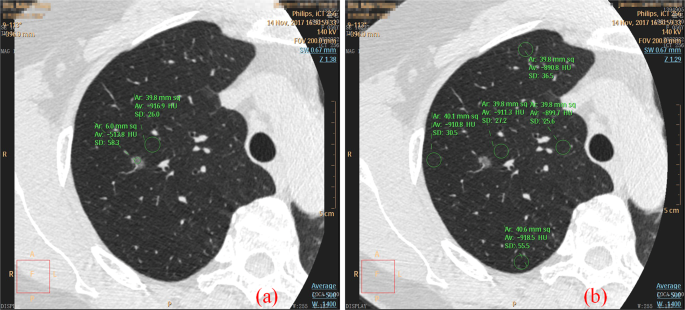

Comparison of imaging scores for the three CT scanning schemes was shown in Table 1. Illustration of ROIs (inner, center, outer, former, posteriori) of the lung fields on the fGGO layer for CT value calculation was shown in Fig. 3(b). The image quality of the scheme G findings has significantly higher score than that of the B-scan and A-scan regarding the margin and internal characteristics (all P < 0.05).

Doctors selected ROIs of fGGO for SNR calculation (Fig. 3(a)). We analyzed the SNR values of different lung field (upper, middle and lower lobe) for the three CT scanning schemes., which are shown in Fig. 6(a–c) shows the total SNR comparison of 30 samples. For scan scheme A and B, SNR of upper and middle lobe are higher than lower lobe, while the SNRs of scan G are similar high at each lung field, also SNRs of scan G are overall higher than scan A and B. The p-values of A versus G, B versus G, and A versus B are 0.041, 0.065, 0.91, respectively.